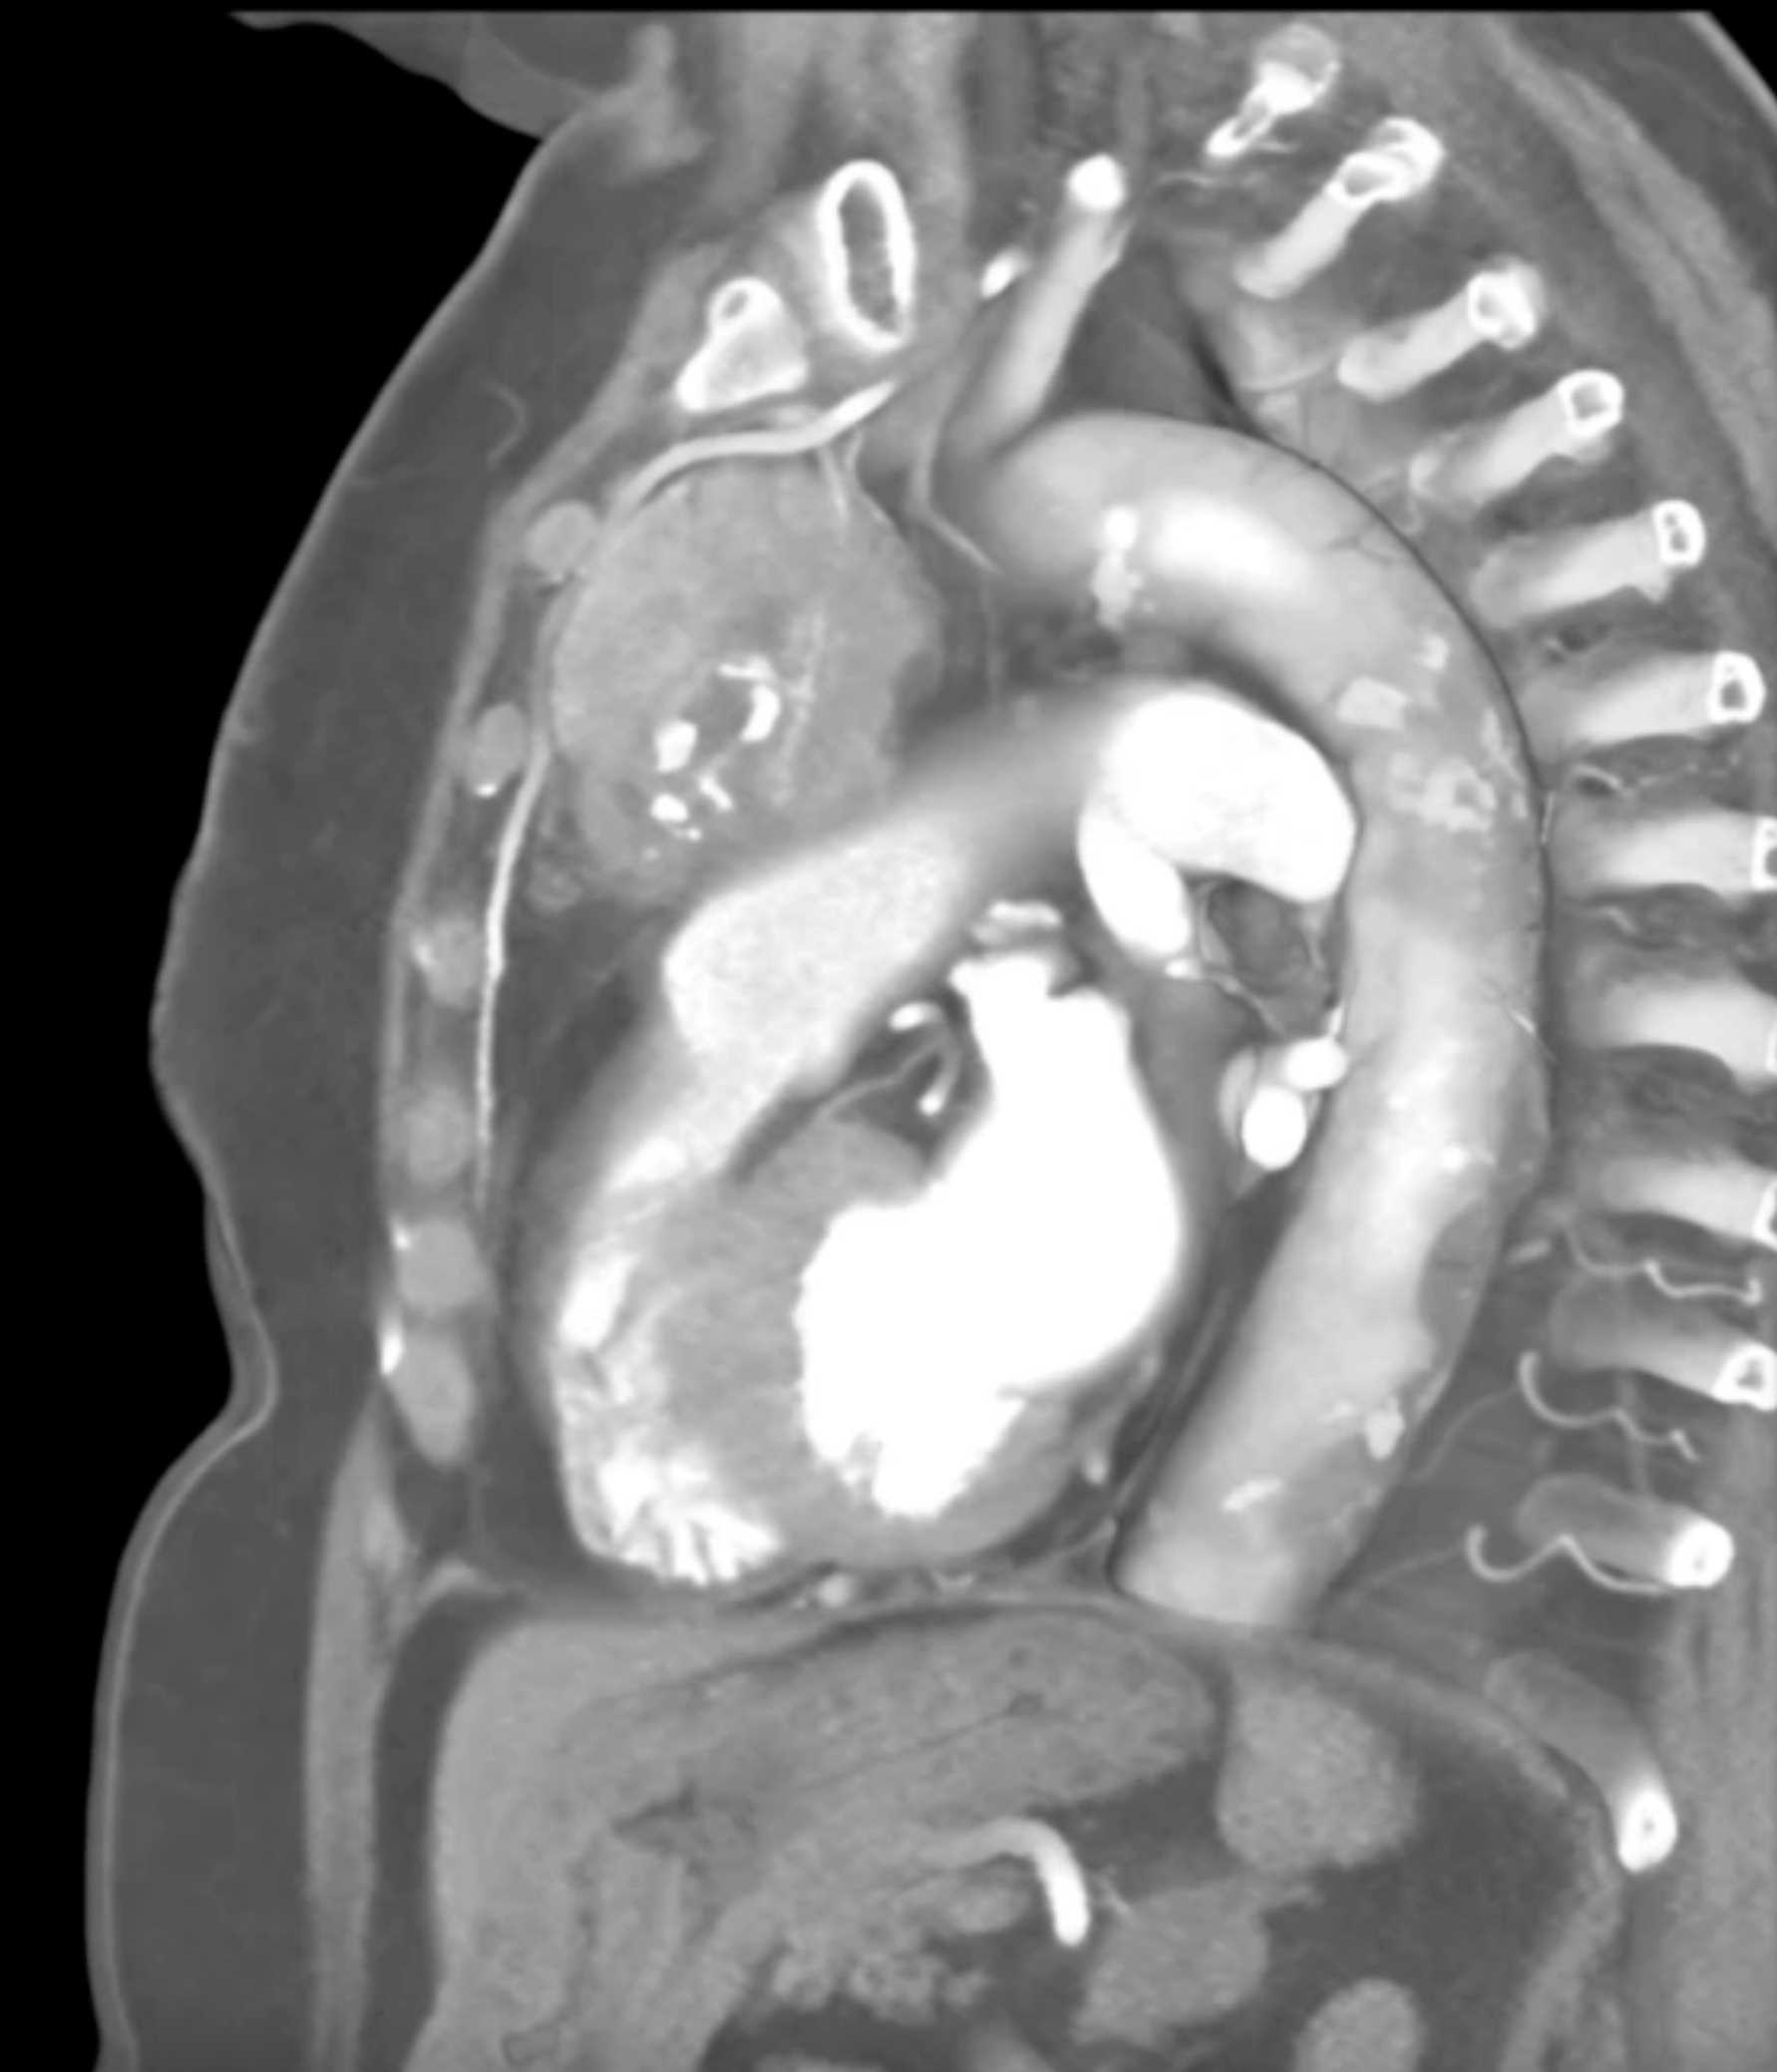

Thymic Carcinoma